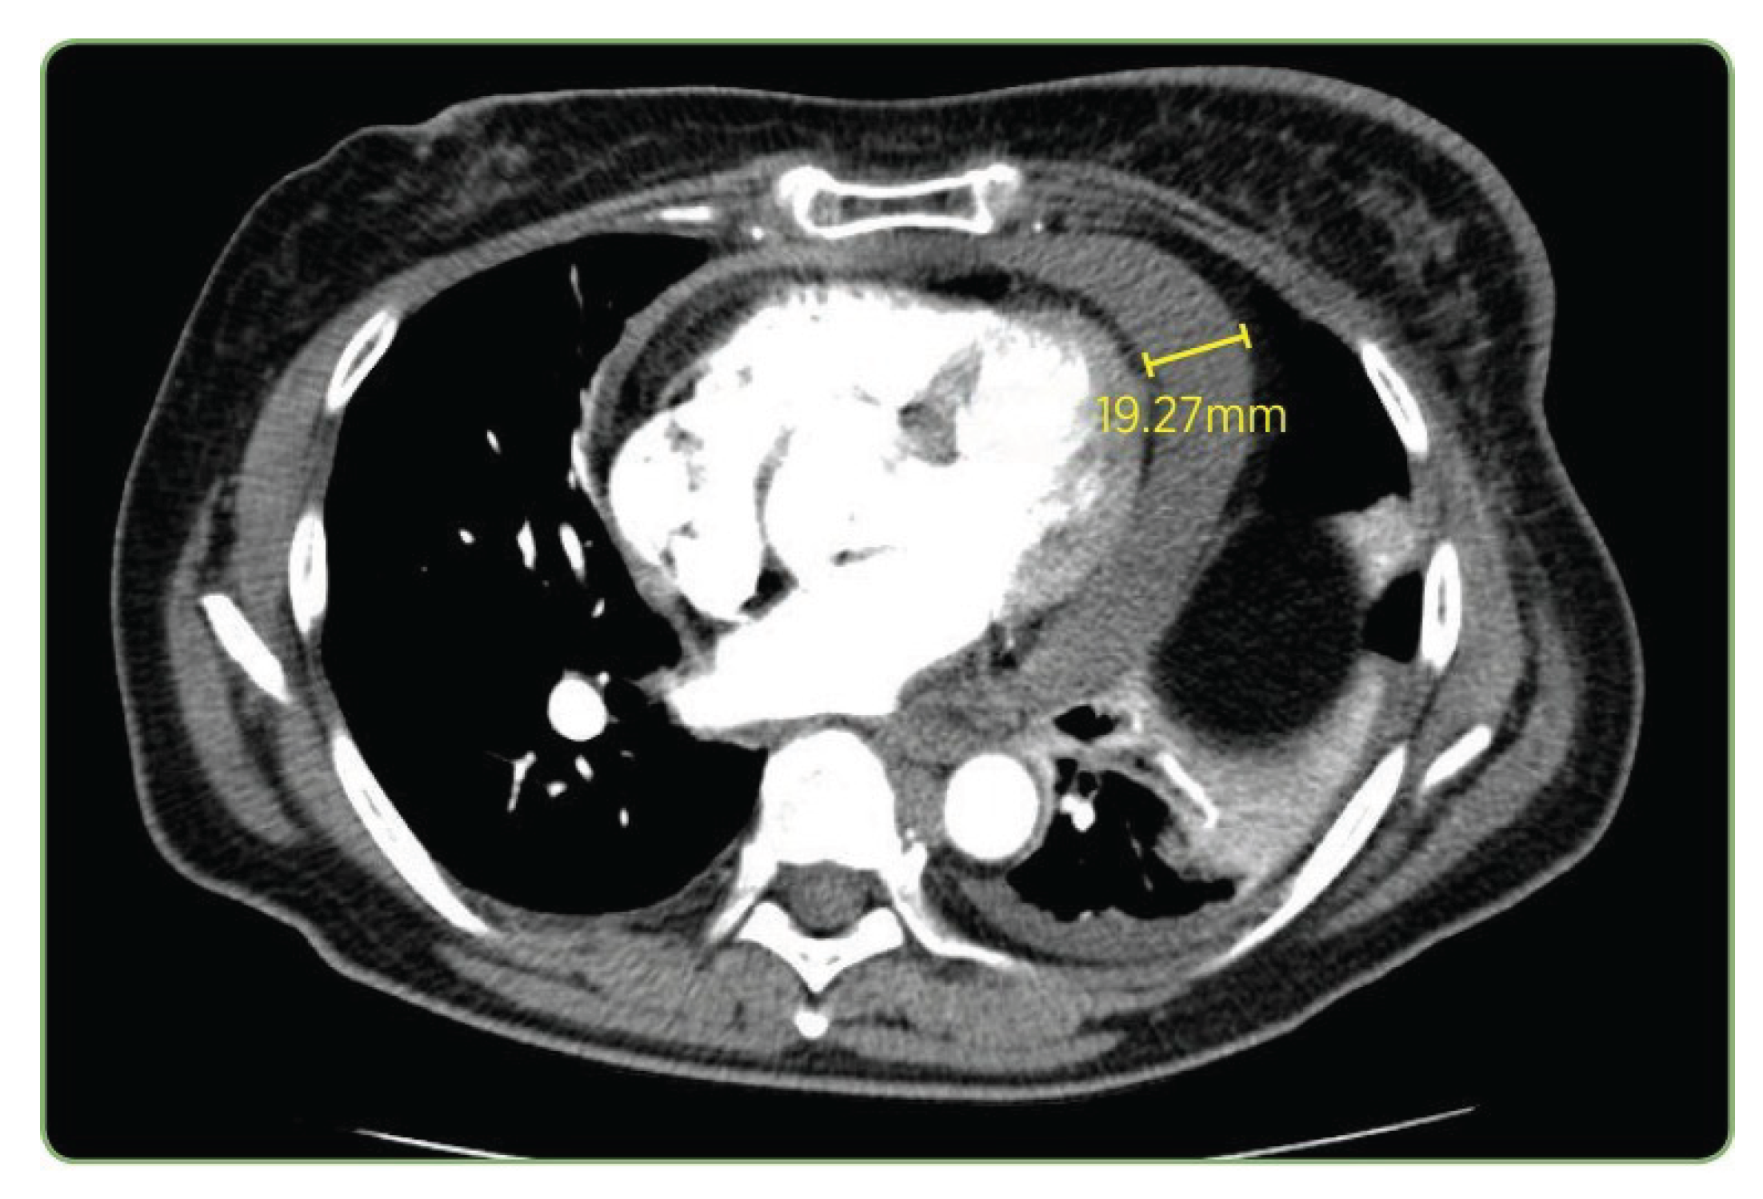

The CT case in Figure 11 and Table 7 exposed more pronounced performance stratification. Only LLaVA-Mistral-7B reproduced all components including the exact measurement (19.27 mm). LLaVA-Vicuna-7B also captured the pathological finding and measurement correctly, although it substituted pulmonary angiogram for pulmonary embolus study, which is a variation in clinical terminology. LLaVA-1.5 and IDEFICS-9B correctly identified both the modality and the pulmonary context, matching the study type, though neither detected the actual pathological finding of pericardial effusion. LLaVA-1.5 incorrectly described a pulmonary embolism in the right lower lobe as the primary finding, while IDEFICS-9B produced a truncated and incomplete description.

Among SVLMs, MoonDream2 correctly identified the modality and general anatomical region (chest) but misinterpreted the finding as a large mass in the right upper lobe. Qwen 2-VL correctly identified the modality but described a vague right-sided mass without proper anatomical context. Both failed to identify the pericardial effusion. Qwen 2.5 failed completely by mislabeling the study as an axial T2 MRI. SmolVLM demonstrated partial success by correctly identifying the modality, chest anatomy, and extracting the precise measurement 19.27 mm, though it completely misattributed the measurement’s clinical context, suggesting surface-level pattern matching without semantic understanding. Thus, the performance degradation in Qwen 2-VL when modality prompting was applied underscores the need for careful validation before implementing augmentation strategies in clinical workflows. Analysis of caption generation across varying complexity levels exposed consistent patterns in model behavior.